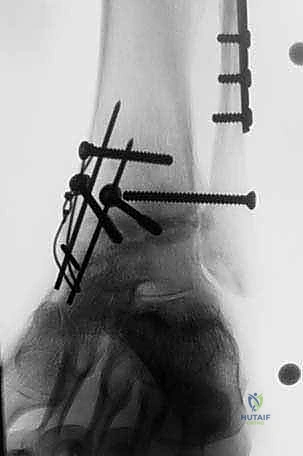

- External Fixator Application for Distraction: Now, let's apply our external fixator. We use a standard distraction device to symmetrically open the joint.

- Pin Placement: Typically, two pins are placed into the distal tibia, parallel to the joint line, and two pins are placed into the talus, again parallel to the joint line. Ensure these pins are placed safely, avoiding neurovascular structures.

- Frame Assembly: Assemble the external fixator frame, connecting the tibial and talar pins.

- Distraction: Gradually distract the joint, aiming for approximately 1 cm of symmetrical distraction. This provides excellent visualization of the entire articular surface and protects the soft tissues during our subsequent bone cuts.

* Rationale: This distraction is vital. It not only improves visualization but also prevents soft tissue impingement during saw cuts and helps maintain appropriate joint space.

4. Placement and Fixation of the Grafts

Now for the moment of truth – seating our fresh osteochondral allografts.

- Graft Seating:

- With the ankle held in a position of plantarflexion, carefully introduce and seat the prepared tibial allograft onto the resected tibial plafond. Ensure it sits flush and stable.

- Next, introduce and seat the talar allograft onto the resected talar dome.

- Remove External Fixator and Assess Stability: Once both grafts are initially seated, we can carefully remove the external fixator.

- Now, gently take the ankle through a full range of motion. Assess for any impingement, instability, or incongruity. The grafts should articulate smoothly and congruently. This dynamic assessment is crucial.

- Fluoroscopic Confirmation of Apposition and Anatomy: